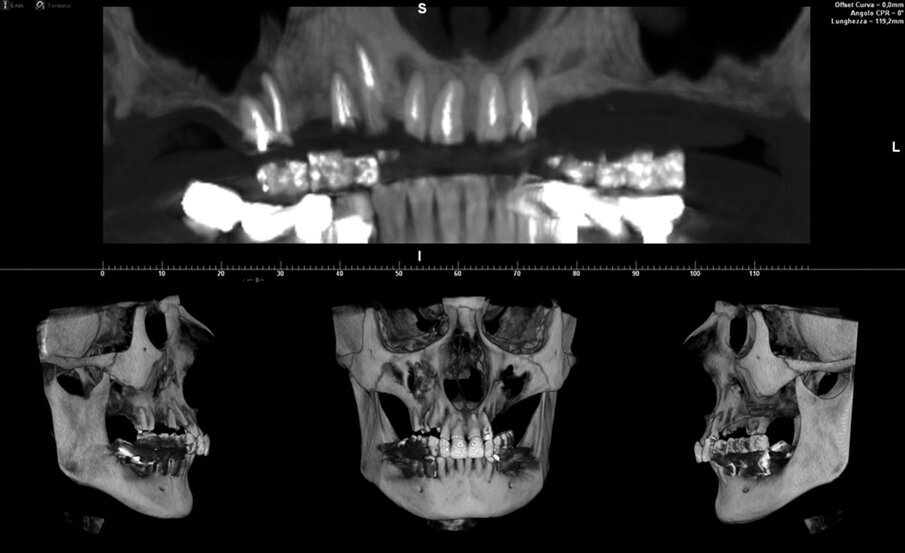

La paziente, di 54 anni, si è presentata al Centro Odontoiatrico Dentalnarco a Trezzano Sul Naviglio, Milano, Italia con tutti gli elementi residui del mascellare superiore compromessi (elementi 1.6, 1.4, 1.3, 1.2, 1,1 nel quadrante destro e 2.1 e 2.2 nel quadrante sinistro) (Fig. 1). A livello anamnestico, la paziente presentava un pregresso episodio di trombosi cerebrale ed era quindi in terapia anticoagulante con warfarin sodico (Coumadin, Bristol-Myers Squibb Srl, Roma, Italia); riguardo al valore INR (dall’inglese International Normalized Ratio), il range terapeutico impostato dai medici curanti era di 3. Avendo la paziente richiesto la massima riduzione possibile in termini di invasività dell’intervento, è stato dunque escluso in questa fase un intervento di grande rialzo di seno nel quadrante 2 e si è optato per un intervento di ridge preservation contestuale alle avulsioni. Per procedere alla corretta elaborazione del piano di trattamento, la paziente è stata sottoposta ad esame CBCT utilizzando un dispositivo ad alta risoluzione (Xmind TRIUM, ACTEON, Milano, Italia) con un FOV di 12 x 8 cm. Considerato il biotipo tissutale sottile della paziente, l’estensione dell’area crestale oggetto di trattamento e l’esiguo spessore della corticale vestibolare (Fig. 2), alla paziente è stato proposto un piano di trattamento che prevedeva l’avulsione di tutti gli elementi, l’innesto di un biomateriale a lento riassorbimento, il posizionamento di 5 impianti in un secondo tempo chirurgico e la riabilitazione definitiva attraverso una protesi fissa con chiavistelli liberamente rimovibile dal paziente. La paziente ha accettato il piano di trattamento e fornito il proprio consenso informato.

Fig. 1_CBCT e ricostruzione tridimensionale del massiccio facciale della paziente. I sette elementi ancora presenti nel mascellare superiore sono compromessi.